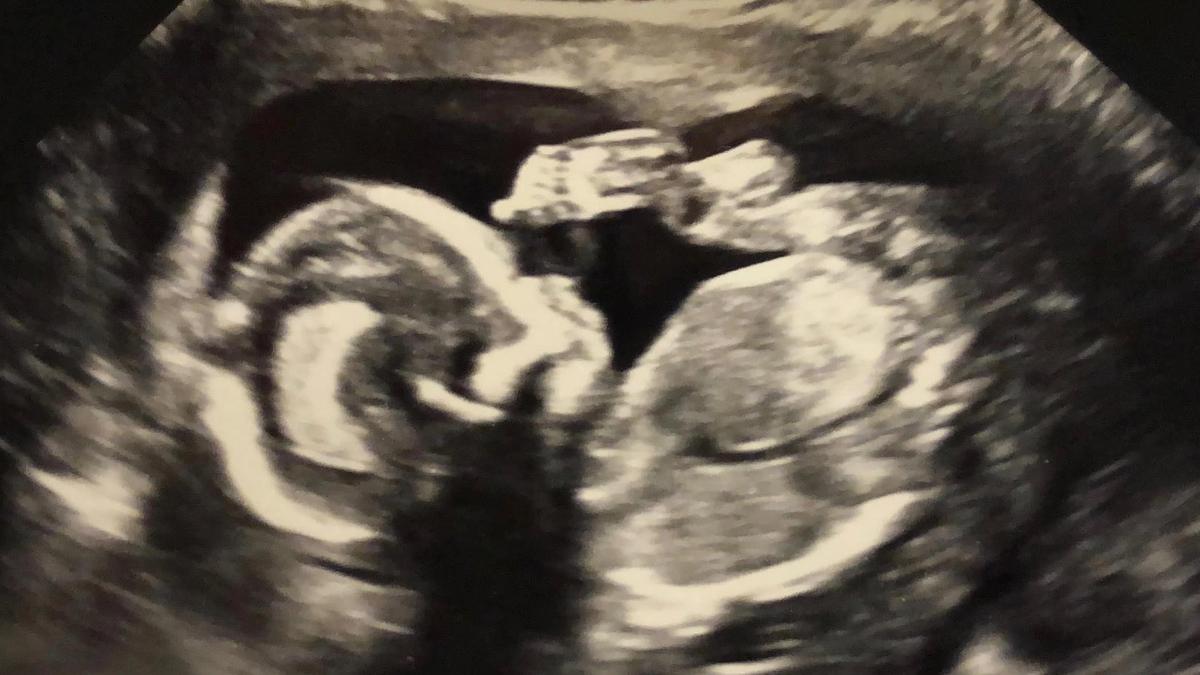

Zaterdagochtend vroeg schrok ik wakker, het voelde alsof mijn vliezen waren gebroken en ik vruchtwater verloor. “Maar dat kan toch nog helemaal niet?”, dacht ik, “Ik moet nog wel even.” Het voelde niet goed, maar ik wilde niet meteen in paniek raken. Twee dagen geleden had ik nog een echo gehad en alles was goed, ons kindje stak nota bene zijn duim op voor de foto. De NIPT inclusief nevenbevindingen was een tijd geleden ook goed, en de ‘gevaren termijn’ was ik al ruimschoots voorbij. De verloskundige kwam langs en na een testje bleek het mogelijk toch vruchtwater. Diezelfde ochtend ging ik naar het ziekenhuis. Vincent was op vakantie en dus kwam mijn zus om mij bij te staan. Na wat routinevragen kwam de verloskundige met een echoapparaat. Ze zette het op mijn buik en zei: “Ik heb even moeite met het kindje te vinden”. Twee dagen ervoor had ik hem nog gezien dus ik dacht meteen: “Hoe kan dat nou, zo’n groot kindje kan toch niet verdwijnen?” Maar ook ik zag vrij snel dat het moeilijk zichtbaar was omdat er nergens ‘zwart’ en dus ‘vruchtwater’ omheen zat. Ze zei het ook direct: “Er zit helemaal geen vruchtwater meer in. Ik ga even met de dokter overleggen.” En weg was ze. Alle lucht werd in één keer uit mijn lichaam gezogen. Het voelde alsof mijn hart eruit gerukt werd. Dit was slecht nieuws.

Na 48 uur was er nog geen bevalling. Vin was inmiddels terug uit het buitenland en we mochten naar een gespecialiseerd ziekenhuis voor een nieuwe echo. Het duurde een eeuwigheid voor we aan de beurt waren. Ergens gaf het wachten ook een fijn gevoel. Zolang er nog niet gekeken is, is mijn kindje nog springlevend en met iedere minuut die wegtikt is het gewoon nog mijn kleine jongetje in mijn buik die het moeilijk heeft, maar het gaat redden. Toen we eindelijk aan de beurt waren en ik ging liggen op de behandelbank zei de echoscopiste nog: “Wat naar allemaal, we gaan eens kijken en dan gaan we bespreken met de arts wat het plan gaat worden”. Toen ik vertelde dat we vanuit het andere ziekenhuis begrepen dat de kansen erg slecht zijn keek ze ons gek aan. “Er zijn tal van opties ik zou niet altijd uitgaan van het meest slechte, dus laten we eerst gaan kijken”. Voor heel eventjes vult je hart zich dan direct met hoop. Maar kort daarna zag ik het meteen. Ze kon het kindje nauwelijks in beeld krijgen. Geen enkel druppeltje vruchtwater. Ons arme jongetje lag helemaal opgekruld. Ze ging op zoek naar het hartje. Heel lief zei ze nog: “Het is wat moeilijker te vinden zo maar niet meteen zorgen maken het kan even duren”. Maar ik wist het al zodra ik het beeld zag. Het is gestopt. Zijn hartje werkt niet meer. Hij is overleden. Ons kindje is er niet meer. En ik heb dat moment niet eens gevoeld als moeder.